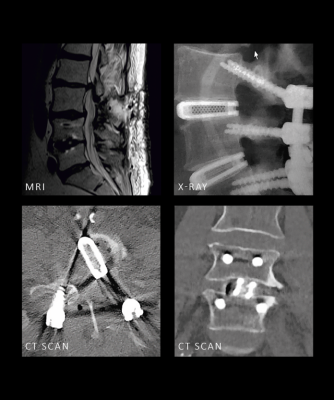

Avec un coefficient de friction élevé pour une stabilité primaire renforcée et une fusion cliniquement prouvée à 12 mois, cette solution offre des performances validées par des publications scientifiques; de la stabilité immédiate au succès à long terme.

La technologie Ti-LIFE favorise une intégration osseuse rapide et efficace, avec une croissance osseuse significative observée dès quatre semaines après l’intervention.